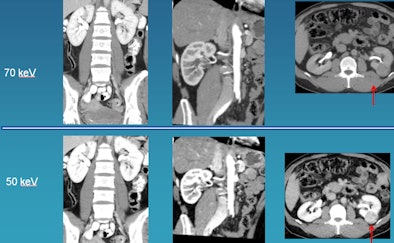

![]() |

| Low-kV imaging improves contrast enhancement, revealing in the case above a renal cell carcinoma at 50 kV that was poorly visualized at 70 kV. |

In the imaging of renal cell carcinoma at 120 kV versus 50 kV, lesion enhancement is maximized at the lower kV setting, he said. In a patient with liver metastases, moving from 70 kV to 50 kV improves tumor definition and also better defines the area around the tumor.

In general, the group has found that 50 kV is optimal for vascular imaging, and 70 kV strikes a nice balance for a combination of vascular and solid visceral imaging, producing good image quality, Sahani said.